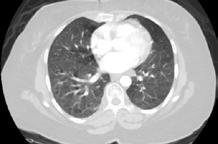

A 58-year-old female with recently diagnosed COVID-19 pneumonia was found to have a dry cough and dyspnoea in the setting of persistent bilateral hilar and mediastinal lymphadenopathy associated with bilateral nodular infiltrates. Of note, she immigrated to the USA from India 10 years prior, with the most recent travel to India 2 years ago. Quantiferon testing upon return to the USA was negative at that time. Workup included bronchoscopy with endobronchial ultrasound revealing non-caseating granulomas with negative stains for acid-fast bacilli (AFB). She was diagnosed with Stage 3 sarcoidosis and initiated on prolonged steroid taper with improvement of symptoms. With taper of steroid dose, however, she developed lymphocyte-predominant exudative effusion with negative cultures, and was reinitiated on a protracted steroid course with rapid symptom resolution. At 4-month follow-up, she had worsening CT findings upon steroid taper, and was started on azathioprine. One month later, she required hospital admission for worsening dyspnoea and fatigue. She was noted to be febrile, tachycardic, and tachypnoeic with worsening

hypoxia. Subsequent CT chest showed progression of bilateral nodular infiltrates with new right upper lobe consolidation and air bronchograms concerning for multifocal pneumonia (Figure 1). Incidentally, she was also noted to have calcified splenic granulomas. She developed rapid clinical deterioration, ultimately requiring mechanical ventilation, pressor support, and continuous renal replacement therapy. Repeat bronchoscopy revealed diffuse alveolar haemorrhage with multiple AFB smears positive for Mycobacterium tuberculosis. She was immediately initiated on quadruple therapy, but unfortunately, despite treatment, developed refractory shock and passed away 2 weeks after initial presentation.

A) Initial adenopathy with peripheral patchy ground glass opacities in the right lung following COVID-19 pneumonia. B) Persistent bulky adenopathy 1 year after initial presentation. C) Extensive nodularity throughout the right lung with increasing confluent opacities in the right upper lobe and stable mediastinal lymphadenopathy 2 years after initial presentation. D) Tuberculosis superimposed on sarcoidosis with progression of nodular infiltrates, worsening right upper lobe consolidation, and air bronchograms with incidental calcified splenic granulomas (not pictured).

Figure 1: CT progression of patient’s sarcoidosis and tuberculosis.